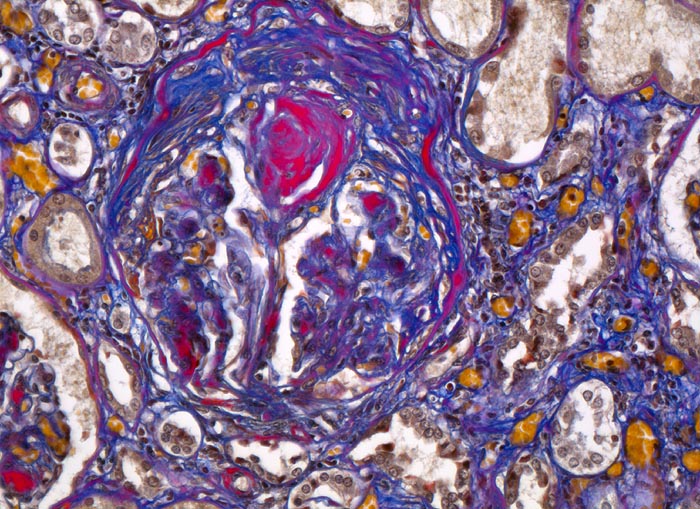

Im allgemeinen ist die Niere infolge von Glomerulumhypertrophie und Tubulushyperplasie vergrössert und derb, die Oberfläche ist granuliert. Bei schwerer Atherosklerose und fortgeschrittener Niereninsuffizienz kann die Niere auch normal gross oder verkleinert sein. Die Kombination von nodulärer Glomerulosklerose, hyalinen Schlingenkappen (=Proteinthromben in den Glomerulumschlingen (> 1916)) oder Kapseltropfen (> 1907) und Arteriolosklerose in Vas afferens und efferens ist beweisend für eine diabetische Nephropathie. Jede einzelne Läsion für sich genommen ist aber unspezifisch. Eine noduläre Glomerulosklerose kann auch vorkommen bei membranoproliferativer Glomerulonephritis (> 2652), Leichtkettenglomerulopathie oder Amyloidose (> 2019). Der nodulären Glomerulosklerose geht bei Diabetikern eine diffuse Glomerulosklerose (> 1906) voraus. Dabei zeigen die glomerulären Basalmembranen und das Mesangium eine progrediente gleichförmige Verbreiterung. Bei der nodulären und diffusen Glomerulosklerose handelt es sich aber wahrscheinlich um zwei pathogenetisch unterschiedliche, sich überlagernde Krankheitsbilder. Typisch bei Diabetikern ist im Unterschied zur arteriellen Hypertonie die Arteriolosklerose von Vas afferens und efferens (> 1911) und oft auch der Vasa recta. Intrarenale Arterien können eine Atherosklerose mit Atheromen zeigen. Subendotheliale Proteinablagerungen teilweise mit Verschluss der Glomerulumschlingen (Schlingenkappen) und knotige Proteinablagerungen in der Bowman'schen Kapselbasalmebran (Kapseltropfen) gehören zu den sogenannten exsudativen Läsionen (> 1919) (> 1920) der diabetischen Nephropathie und führen zu Synechien sowie zur globalen Glomerulosklerose. Gleichzeitig mit den Glomerulumveränderungen treten tubuläre Basalmembranverbreiterungen auf, später eine Tubulusatrophie und interstitielle Fibrose mit Begleitentzündung. Auch die Basalmembranen der peritubulären Kapillaren sind verdickt.

• Verbreiterung des Mesangiums mit Ausbildung von Knoten(noduläre Glomerulosklerose).

• Exsudative Läsionen: Hyaline Schlingenkappen (Proteinthromben in Glomerulumschlingen, im virtuellen Präparat nicht sichtbar) und Kapseltropfen (Proteinablagerungen im Bowman’schen Kapselraum).

• Arteriolosklerose von Vas afferens und efferens (Gefässwandhyalinose durch Ablagerung von Plasmaproteinen und Lipiden in der Gefässwand).

• Verdickte Basalmembranen der peritubulären Kapillaren.

• Verbreiterung der tubulären Basalmembran.

• Tubulusatrophie mit interstitieller Fibrose und Begleitentzündung.